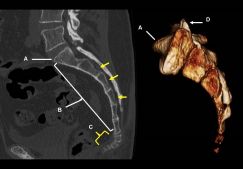

Основные причины смещения копчика, методы диагностики и лечения

Основные признаки смещения копчика, варианты смещения. Методы диагностики, первая помощь. Медикаментозное и хирургическое лечение, прогноз, последствия.